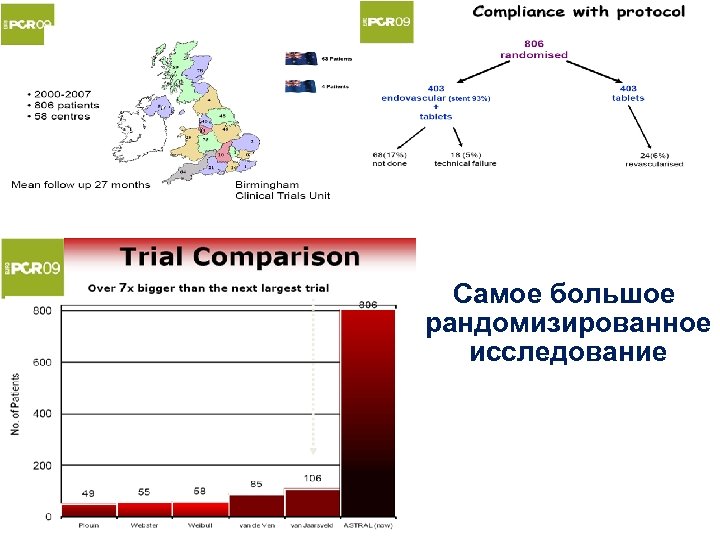

Самое большое рандомизированное исследование

Самое большое рандомизированное исследование